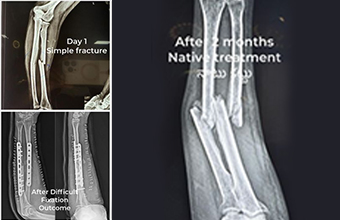

But recently, the number of patients suffering from complications due to outdated methods has made this mission more urgent. In areas around Tirupati, like Puttur/Eslapuram and Kallur, we see many victims of these outdated treatments. The issue affects everyone, regardless of education or social status. Many people avoid surgery out of fear or cost concerns, while others trust ancient methods like Shalya medicine. What they don’t realize is that these practices often cause more harm than good. One of the biggest misconceptions is that all fractures should be treated the same way. I’ve seen patients with minor injuries treated with outdated methods like chicken wire or makeshift bandages. These methods are not just ineffective—they also undermine the expertise of modern orthopedic care. I’ve witnessed the consequences of this firsthand. Bones heal in misaligned ways, and patients suffer nerve and blood supply damage from improperly applied implants. By the time these patients seek treatment, it’s often too late for a simple fix. Some argue that surgery is too expensive, but free treatment is available at local hospitals or at Tirupati Ruya hospitals. The real cost is the long-term damage caused by avoiding proper care. Attempting to fix complications with outdated methods only makes things worse. In some cases, what could have been a minor procedure turns into a complex surgery with poor results.